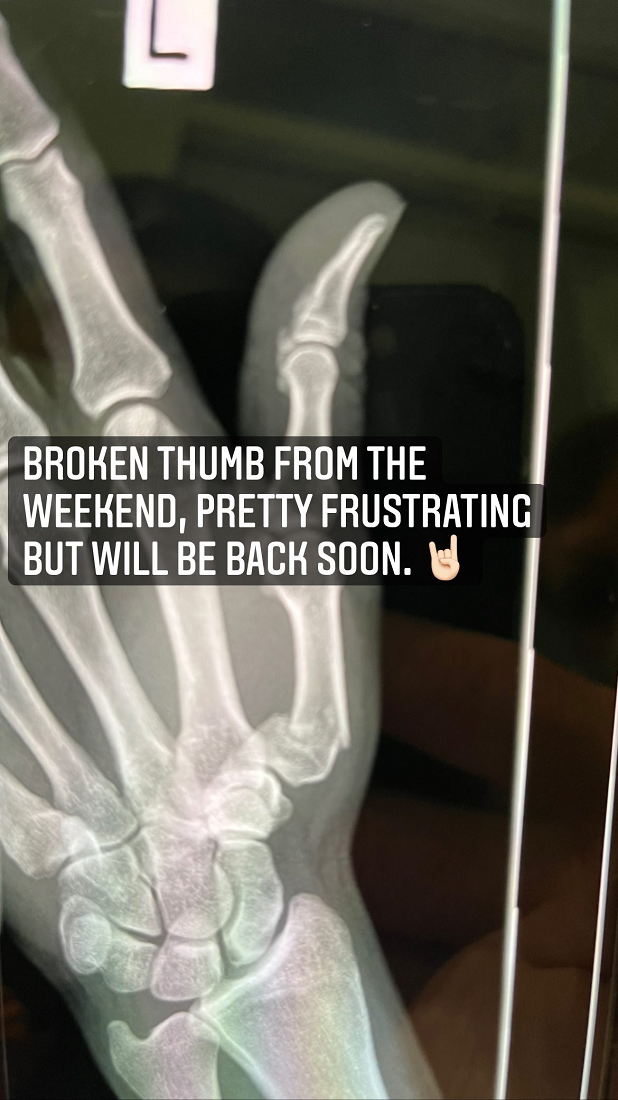

From Brodie Retallick's instagram

1bff2dde-7433-4fb2-8308-e4b67eff6843-image.png